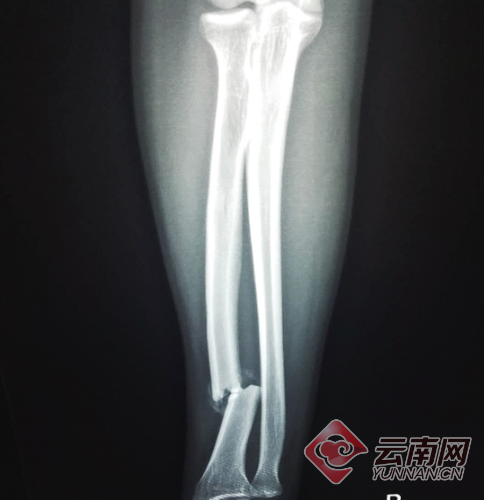

“帶我去醫(yī)院吧?!泵鎸π』锏囊?駕駛員開車將其送到西山區(qū)人民醫(yī)院。照了胸片和CT,CT結(jié)果顯示傷者右手橈骨骨折。